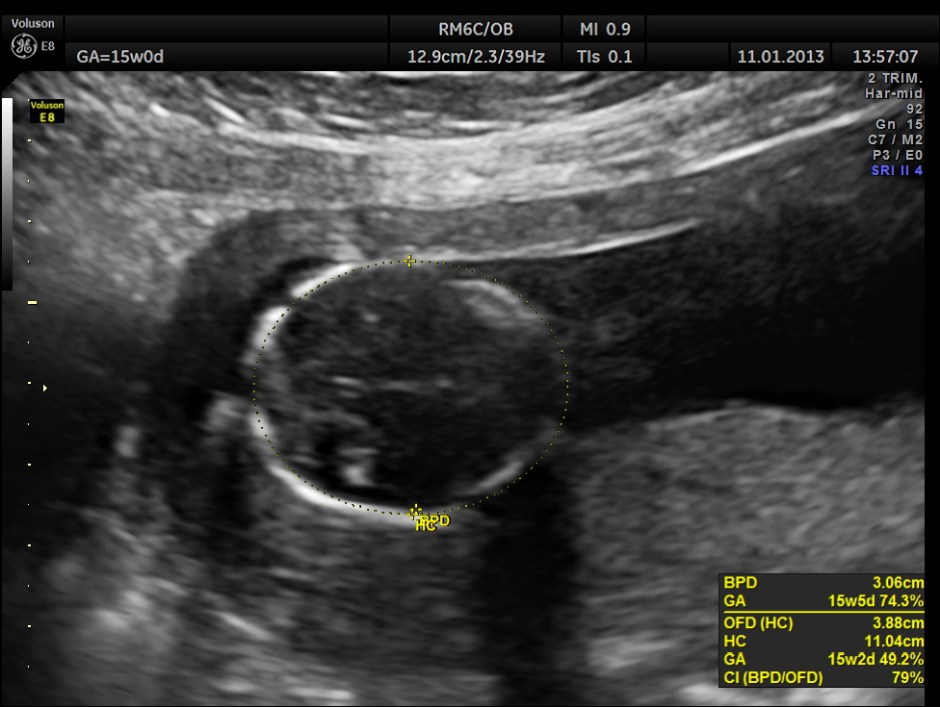

This was a 28 year old lady , primi gravida , who presented with acute lower abdominal pain . Her gestational age was around 15 to 16 weeks.

The pregnancy scan was otherwise normal.